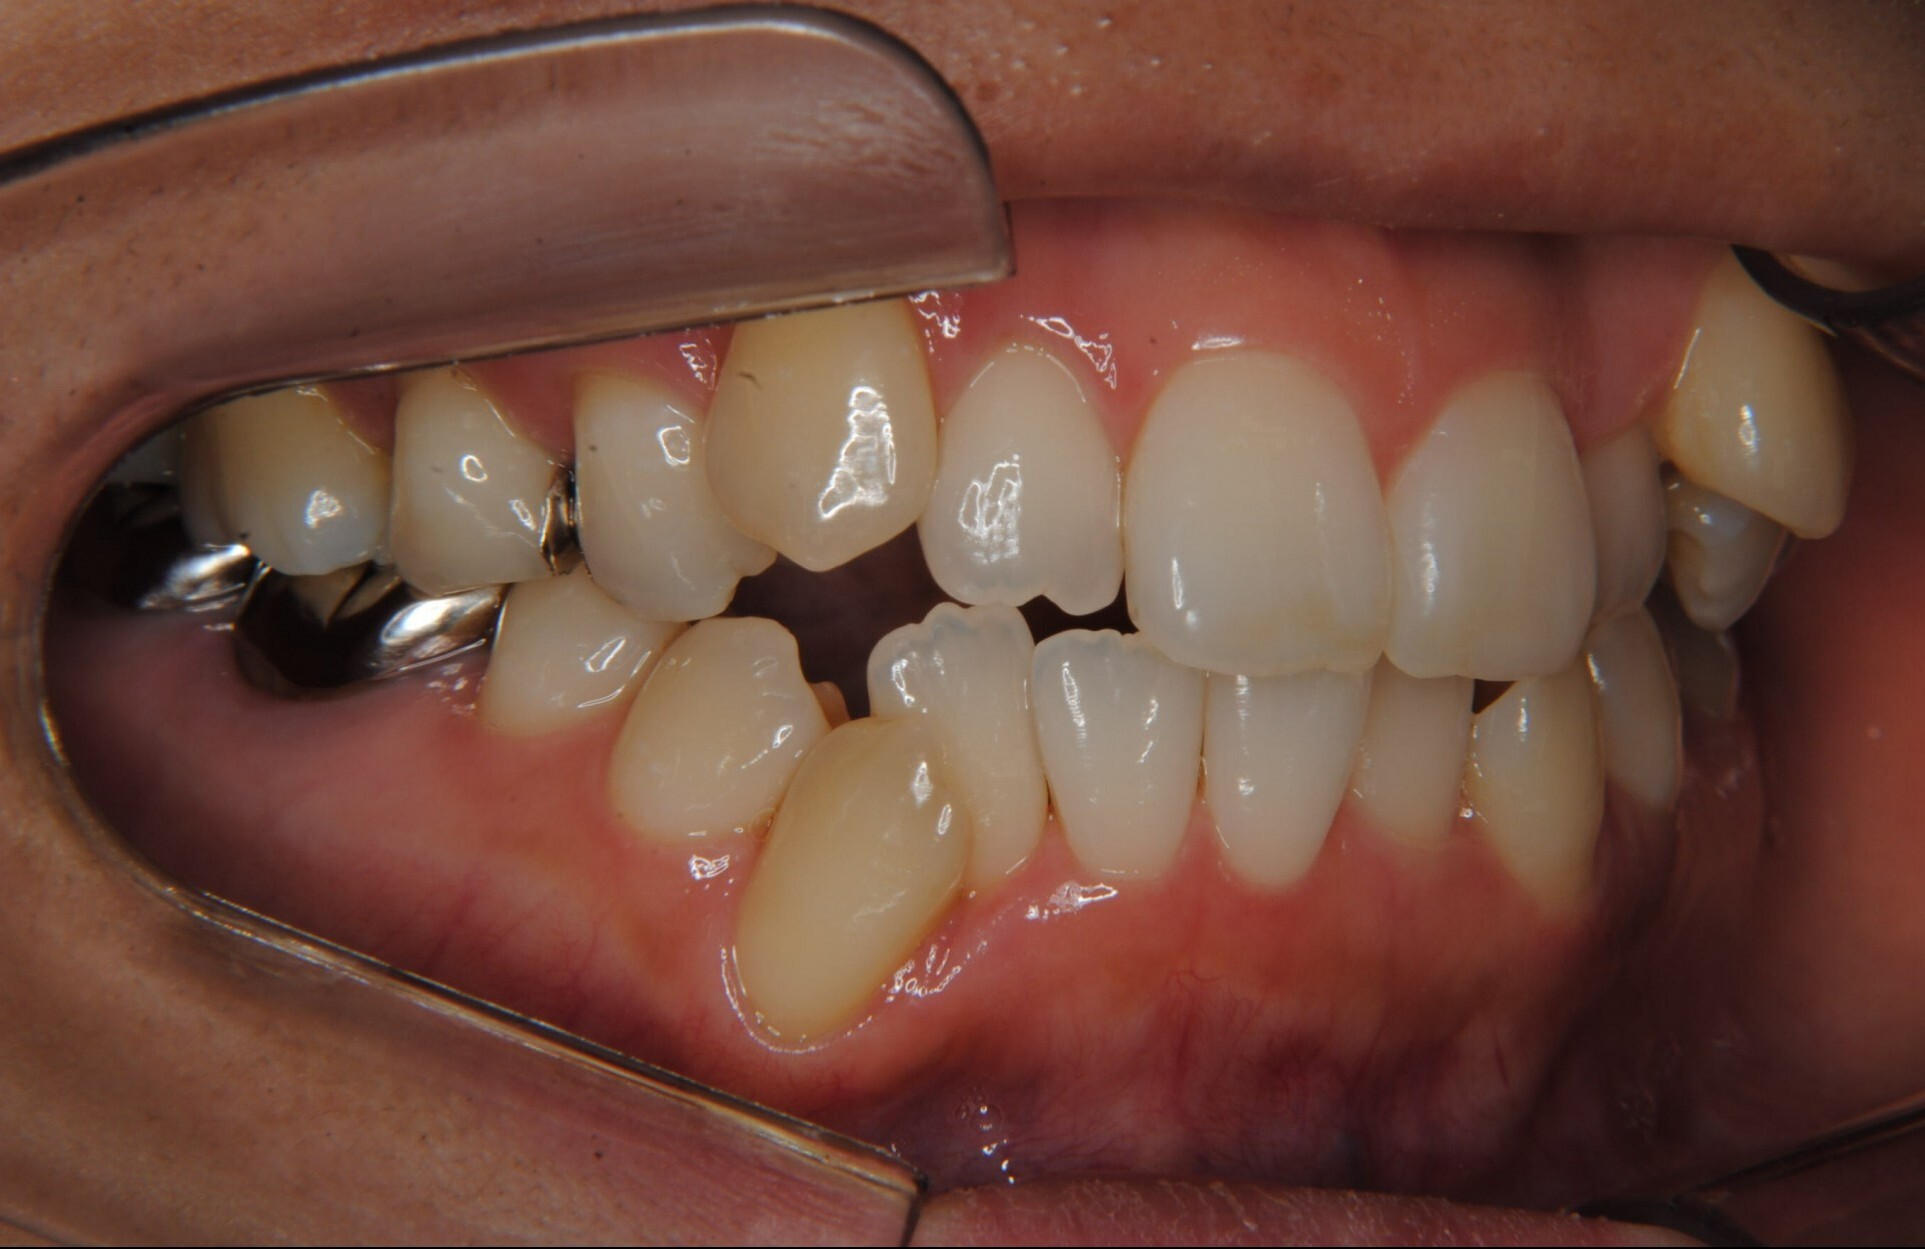

①主訴:八重歯、前歯のガタガタ、真ん中の不一致を治したい

②診断名:AngleⅠ級叢生

⑤抜歯部位:上下左右第一小臼歯

⑧リスクと副作用:マルチブラケット装置(T21ブラケット)を初めてつけてから4日間、食事の時におもに前歯が少し痛かったとのことでした。治療後のエックス線写真で、歯根吸収はほとんど観察されず、歯肉を診ると残念ながら下顎前歯部に歯肉退縮(ブラックトライアングル)が生じていました。しかし、通常下顎前歯部は下唇に隠れてむき出しにはなっていないので、ご本人はあまり気にされていないご様子でホッとしています。